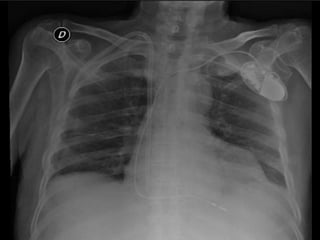

CARDIOPULMONAR:

Ruidos cardiacos rítmicos, no se auscultan soplos,

disminución del murmullo vesicular basal, disneico

Se observa tumefacción en hemitórax anterosuperior izquierdo

correspondiente a marcapasos

•   SS Rx de torax, laboratorios y EKG